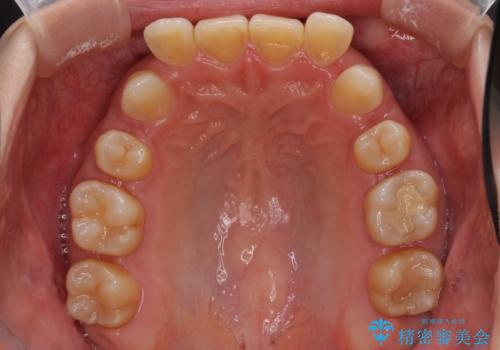

下顎2前歯の欠損 インビザラインによる抜歯矯正

- 下顎前歯欠損による歯列不正を気にして来院された患者様です。

下顎の歯列が小さく、下顎前歯が隠れてしまう過蓋咬合(ディープバイト)であったため、

①下顎歯列を拡大し、欠損部に2歯分のインプラント補綴をおこなう

②上顎左右第一小臼歯2本を抜歯、下顎歯列を拡大し、欠損部に1歯分のインプラント補綴をおこなう

③上顎左右第一小臼歯2本を抜歯し、下顎はスペースを閉じる

マウスピースでの抜歯矯正特有の抜歯スペースに向かって奥歯が傾斜する動きが顕著に表れ、ディープバイトは改善されませんでした。

前歯のみが強く接触し、奥歯で咬めない期間も続いたため、ワイヤー装置などを補助的に使用し、何とか終了させることができました。